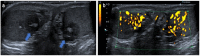

Pre- and post-pubertal testicular tumors are two distinct entities in terms of epidemiology, diagnosis and treatment. Most pre-pubertal tumors are benign; the most frequent are teratomas, and the most common malignant tumors are yolk-sac tumors. Post-pubertal tumors are similar to those found in adults and are more likely to be malignant. Imaging plays a pivotal role in the diagnosis, staging and follow-up. The appearance on ultrasonography (US) is especially helpful to differentiate benign lesions that could be candidates for testis-sparing surgery from malignant ones that require radical orchidectomy. Some specific imaging patterns are described for benign lesions: epidermoid cysts, mature cystic teratomas and Leydig-cell tumors. Benign tumors tend to be well-circumscribed, with decreased Doppler flow on US, but malignancy should be suspected when US shows an inhomogeneous, not-well-described lesion with internal blood flow. Imaging features should always be interpreted in combination with clinical and biological data including serum levels of tumor markers and even intra-operative frozen sections in case of conservative surgery to raise any concerns of malignity. This review provides an overview of imaging features of the most frequent testicular and para-testicular tumor types in children and the value of imaging in disease staging and monitoring children with testicular tumors or risk factors for testicular tumors.